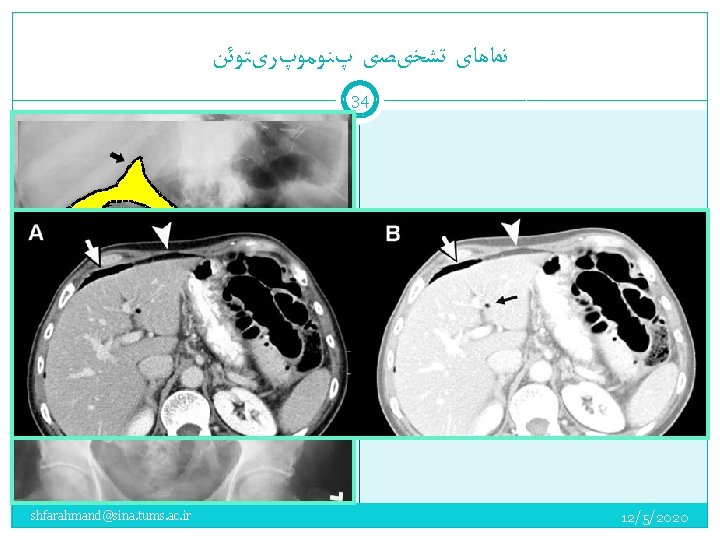

ﻧﻤﺎﻫﺎی ﺗﺸﺨیﺼی پﻨﻮﻣﻮپﺮیﺘﻮﺋﻦ 33 Upright chest radiograph Left lateral decubitus abdominal radiograph Lateral chest radiograph Pneumogastrogram—NG air insufflation Supine abdominal radiograph (massive free air) CT Ultrasonography shfarahmand@sina. tums. ac. ir 12/5/2020